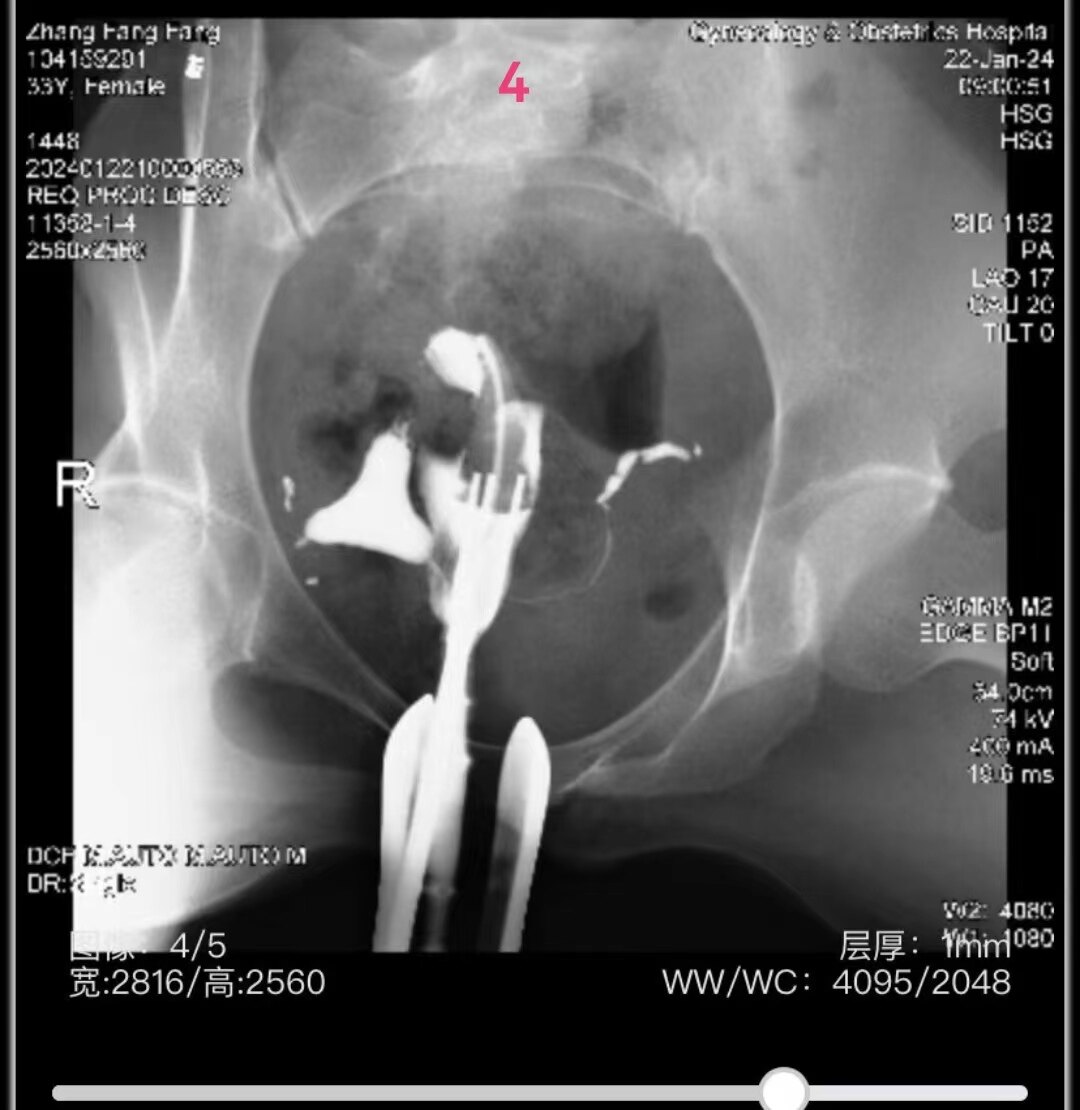

4.jpg

左侧输卵管显影至伞部,右侧输卵管显影至壶腹部近段。造影剂返回到阴道